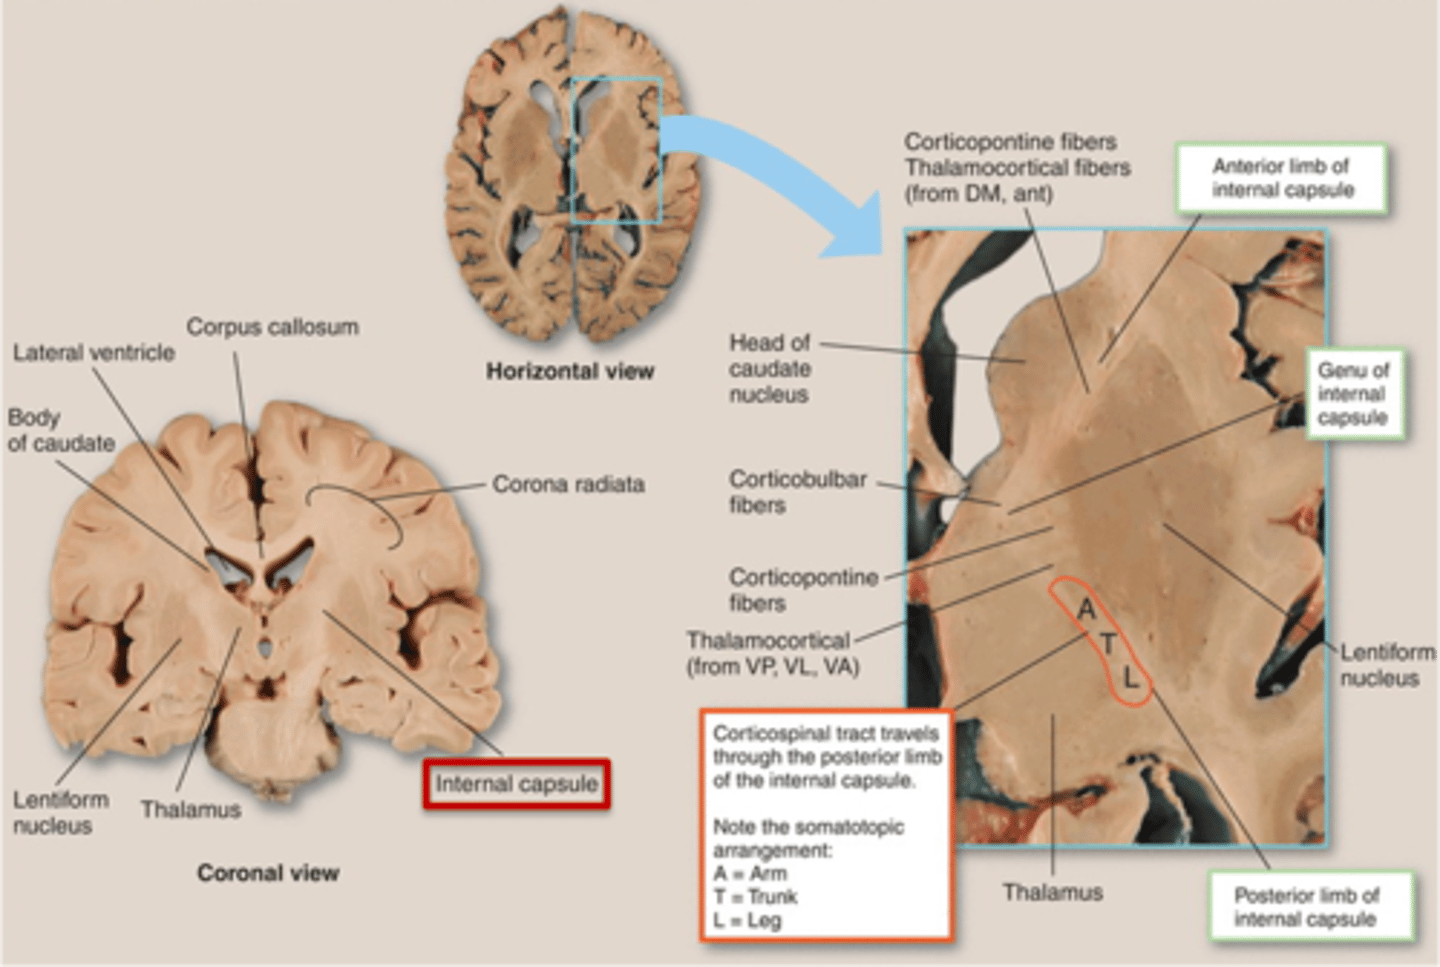

what are 3 key white matter structures found in the cerebrum?

1. corpus callosum

2. corona radiata

3. internal capsule

what cerebral white matter structure is a large bundle of nerve fibers that connects the left and right cerebral hemispheres, allowing them to communicate?

corpus callosum

what is the fan-shaped cerebral white matter sheet that is continuous ventrally with the internal capsule?

corona radiata

what cerebral white matter structure is a tract that carries sensory and motor information to and from the cerebral cortex?

internal capsule

what cerebral white matter structure is found between the basal ganglia?

internal capsule

what are the 3 regions of the internal capsule?

1. anterior limb

2. genu

3. posterior limb

what are the 3 parts of the basal ganglia? what runs between them?

1. caudate nucleus

2. putamen

3. globus pallidus

internal capsule

what part of the basal ganglia is the C-shaped structure that is most medial?

caudate nucleus

what part of the basal ganglia is medial to the putamen?

globus pallidus

the putamen and globus pallidus of the basal ganglia are collectively called the _______________ nucleus

lentiform